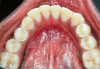

Table 1 presents descriptive statistics for the demographic characteristics of the participants: 83.33% of the study population were aged 18 to 24 years, while 16.66% were aged 25 to 30 years, and 20% of the participants were male while 80% were female, indicating a skewed distribution. Figure 4 through Figure 6 illustrate lingual AG of a representative male subject, and Figure 7 through Figure 9 depict that of a female subject. The mean, standard deviation, mode, median, and extremes for all the mandibular permanent teeth are recorded in Table 2. The extreme measurements were in the range of 0 mm to 10 mm, considering all teeth and subjects. The width of lingual AG varied with each tooth, with the mandibular first molar having the widest average width (6 mm ± 1.3 mm) followed closely by the second molar (5.8 mm ± 1.2 mm). The central incisors (0.5 mm ± 0.5 mm) showed the narrowest zone along with the highest maximum number of teeth without detectable AG (Table 3). The width of AG did not significantly differ between the sexes (Table 4). The overall indicative schematic of lingual AG is shown in Figure 10 and Figure 11.

Fig 4 through Fig 6. Lingual attached gingiva in a male subject: Fig 4 = left side.

Figure 4

Fig 5 = middle.

Figure 5

Fig 6 = right side.

Figure 6